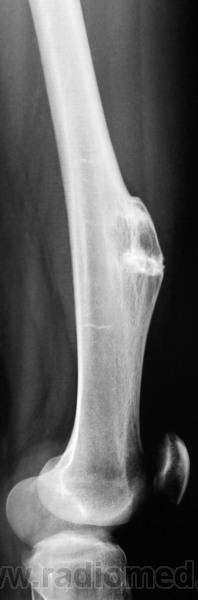

Тянет на остеому, с учетом ободка склероза с костной структурой опухоли.

Экзостоз.

думать о фиброзной дисплазии: возраст, пол, локализация и сама рентген. картина. Хотя экзостоз тоже "держу в уме".

Вы правы уважаемый коллега.

Была выставлена остеохондрома

Вот снимки 3-х летней давности.